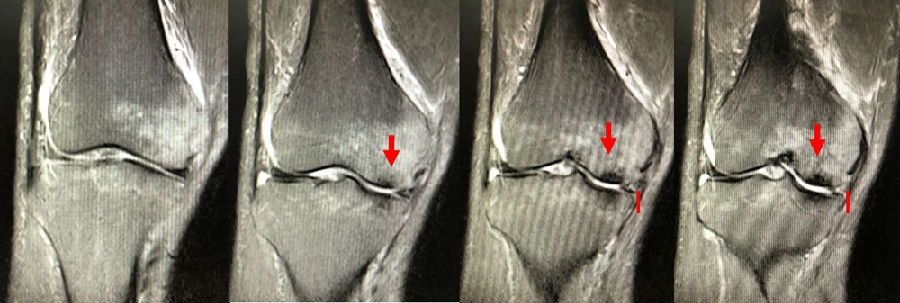

目前SONK诊断最常用的分期方法是1979年Koshino提出的分期法。Koshino分期基于临床和影像学的结果,将SONK分为四个阶段:

Ⅰ期:患者有膝关节症状,但影像学正常;

Ⅱ期:X线显示负重区变平,软骨下信号升高,周围有骨硬化;

Ⅲ期:受影响区域扩大和软骨下塌陷;

Ⅳ期:病变周围骨硬化和髁突周围骨赘形成的退行性阶段。

1979年Koshino分期